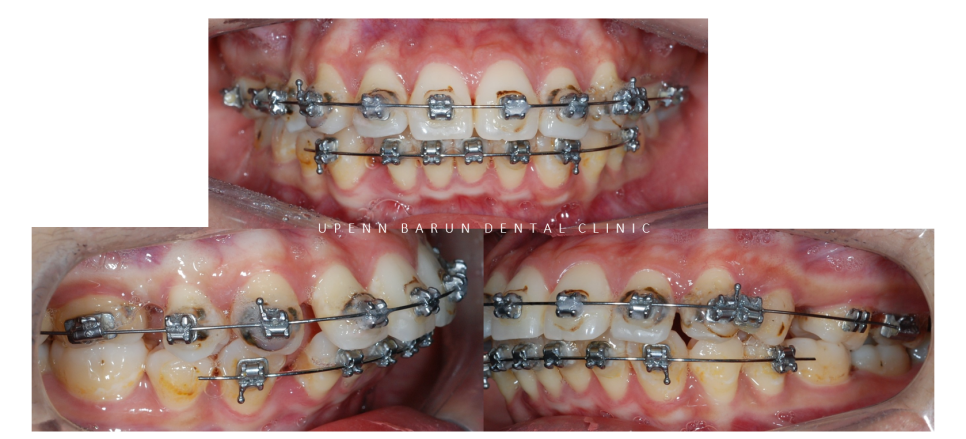

교정 전 사진

환자분께서는 처음 저희 병원에 방문하셨을때

치아가 바깥쪽으로 기울어져

돌출정도가 심하신 상태셨습니다.

윗니2개, 아랫니 1개 총 3개의 작은어금니가 결손치로

균형을 위해 아래 한개의 작은 어금니 발치가 필요한 상황이셨습니다.

완벽함을 추구하는 닥터킴이 기존 교정장치를 제거하고

이상적인 교정치료를 위해 새로 장치를 부착해 시작해 드렸는데요.